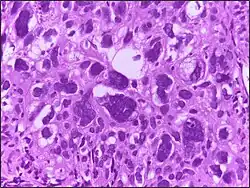

Micrograph showing large cells. H&E stain.

Large cell is a term used in oncology. It does not refer to a particular type of cell; rather it refers to cells that are larger than would be normally expected for that type. It is frequently used when describing lymphoma and lung cancer.